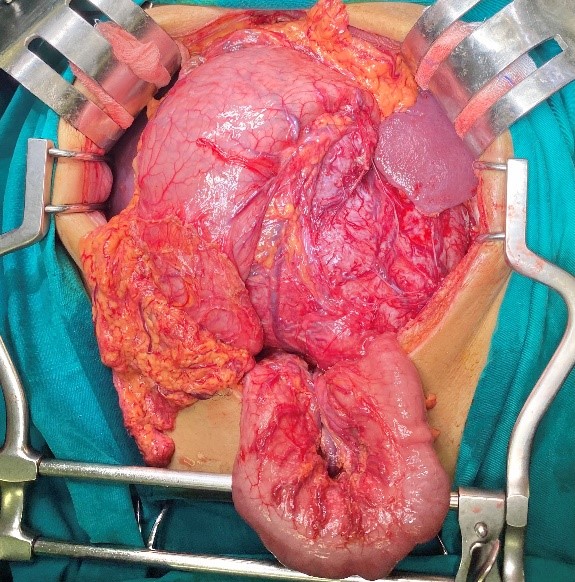

Hình 2: Hình ảnh khối GIST dạ dày xâm lấn thân và đuôi tụy

Bệnh nhân đã phải trải qua một cuộc phẫu thuật lớn: mổ mở cắt cả khối gồm toàn bộ dạ dày, thân đuôi tụy và lách, ca mổ phức tạp, tuy diễn ra thành công ngoài mong đợi nhưng chặng đường tiếp theo với anh N sẽ nhiều khó khăn, nguy cơ bệnh dễ tái phát hoặc di căn…

Trường hợp thứ nhất: Bệnh nhân N, nam 47 tuổi. Tiền sử viêm dạ dày nhiều năm, điều trị không thường xuyên. Khoảng 6 tháng gần đây, bệnh nhân thấy đau tức vùng thượng vị, hay đầy bụng, ăn uống kém hơn. Bệnh nhân tự mua thuốc điều trị viêm dạ dày nhưng không đỡ, đến khi tự sờ thấy khối ở vùng thượng vị mới quyết định đi khám tại Khoa Phẫu thuật Tiêu hóa – Gan mật tụy, Bệnh viện Bạch Mai và được chẩn đoán: GIST dạ dày, tuy nhiên khối u lớn, ở giai đoạn muộn nên đã xâm lấn vào thân đuôi tụy.